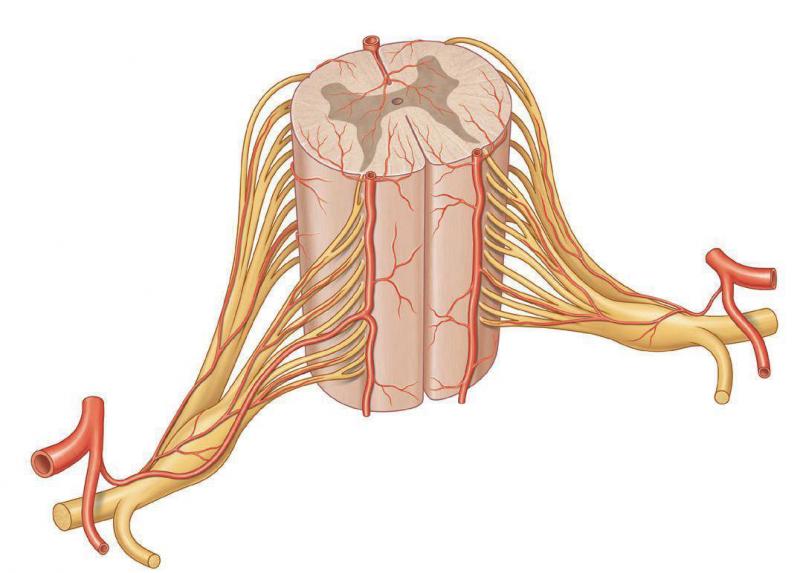

Arterias radiculares

Existen 62 arterias radiculares que presentan una disposición metamérica. Nacen en el cuello de las arterias vertebrales, en el tórax a partir de las intercostales posteriores (ramas de la aorta torácica), en la región lumbar de las lumbares y en la pelvis de las arterias sacras. Cada una de ellas penetra en el conducto vertebral por el foramen intervertebral y se divide en dos ramas, anterior y posterior, para la raíz correspondiente.

Arterias espinales

Han perdido la disposición metamérica se distinguen:

- Dos arterias espinales anteriores, originadas de cada arteria vertebral a nivel del foramen magno, se reúnen en un solo tronco situado en la fisura mediana anterior.

- Dos arterias espinales posteriores, originadas de cada arteria cerebelosa posteroinferior, vuelven a descender a lo largo de los surcos dorsolaterales.

- Arterias radiculomedulares, provienen de las arterias espinales cuyas ramas alcanzan a la médula.

Se observan además dos o tres arterias para la intumescencia cervical provenientes de la arteria vertebral.

La arteria medular segmentaria anterior mayor (arteria radicular magna de Adamkiewicz) que irriga la intumescencia lumbosacra, es unilateral. Se origina en una de las últimas arterias intercostales o en una de las primeras arterias lumbares. En su trayecto describe un arco de convexidad superior, antes de dirigirse hacia el cono terminal.

En la región torácica, el aporte arterial es insuficiente, reducido por lo general a una sola arteria radiculomedular proveniente de la quinta, sexta o séptima arteria intercostal posterior.

Alrededor de la médula observado e un corte horizontal se describe un círculo arterial que reuniría la arteria espinal anterior con dos arterias espinales posteriores. Este círculo existe muy raramente.

En sentido vertical, no existe arteria espinal anterior o posterior extendida a lo largo de toda la médula, reforzada por una rama radicular a nivel de cada segmento, como se describe clásicamente. En realidad, este dispositivo existe a nivel de las intumescencias cervical y lumbosacra, bien vascularizadas, pero desaparece a nivel de la médula torácica. No hay una disposición anatómica perimedular, horizontal o vertical, continua y constante.

La vascularización arterial de la médula es muy precaria y susceptible de ser suspendida por una ligadura o por la obliteración de una sola arteria radiculomedular.

En el interior de la médula, de las arterias que están situadas profundas a la piamadre emergen ramas arteriales, superficiales o profundas,

en especial de la arteria espinal anterior y también de las arterias posteriores. Estas ramas son terminales.